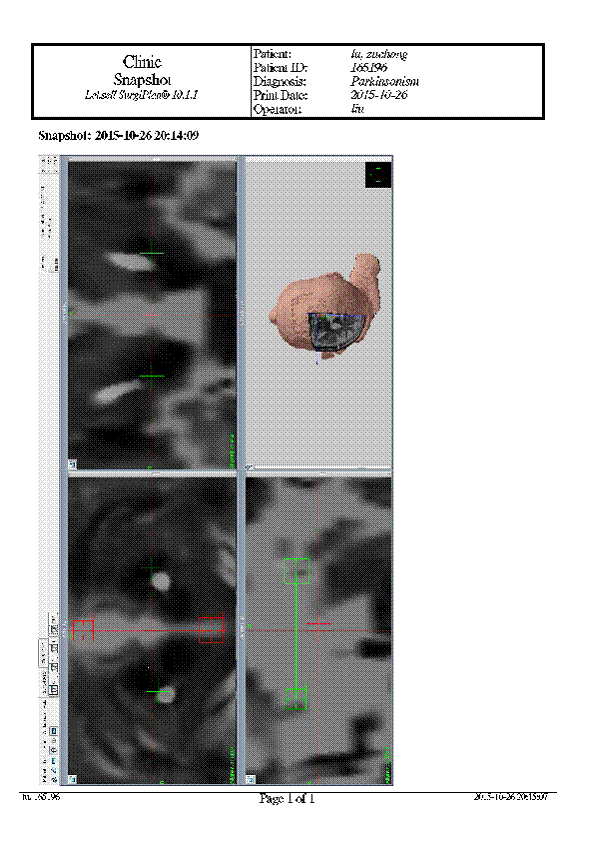

去年底,卢先生接受了脑深部电刺激术(DBS),靶点选择双侧丘脑底核(STN)。手术前,先通过导航系统,精准的测算出患者的靶点部位。术中,医生通过立体定向导航系统+Leadpoint记录仪联合精准的定位到患者的靶点。局麻下唤醒患者并与之交谈,用电刺激器调整参数,通过电流刺激症状,密切注意着患者的应答,肢体动作改变和术中电生理检测仪。调整刺激器的参数。患者可感受肢体的变化,震颤和僵直的改变特别明显,患者感觉满意。然后在全麻的情况下,把导线和刺激系统埋入皮下隧道,手术过程顺利完成。

术后,卢先生没有觉得不适,恢复情况良好。1个月以后,卢先生返回医院接受DBS开机调控,左侧STN电压2.0v,右侧STN电压1.5v,脉宽60us,频率130Hz。关期开机后,卢先生的运动症状明显改善,双侧震颤基本消失,可独立起立行走,未服药状态维持开期3个小时后逐渐进入关期,医生予以原剂量美多巴后可迅速恢复开期。

术后图像